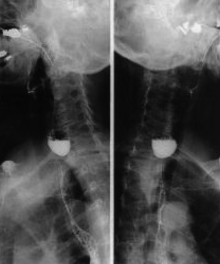

Image TOGD d'une megaoesophage sur

le cliche de face et OAD . Bord lisse et

aperistaltisme ., la retressisement a inferieure est

image en queue de radis |

Megaoesophage en face

et en profile OAD |

A etat tardive oesophage dilate et

alonge en forme de petit chaussette . |